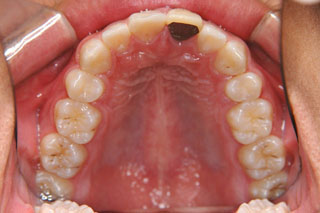

2年半ほどの治療で、装置を撤去し保定治療に移行しています。飛び出ていた前歯も、下の歯と正しく噛めるようになりました。口元の突出も消え、口唇閉鎖時に前歯が覗いて見えるという事も無くなりました。

保定治療に移行してから3年半が経過しました。上の顎に生えてきた親不知は下の顎の奥歯と噛み合うようになりましたが、下の親不知は、斜めに埋まっていましたので、噛み合わせへの変化を防止するためにも早めに抜いて貰いました。矯正治療ではなるべく長期に渡って、管理を行いますが、2年3年と大きな変化が無く、緊密な噛み合わせが確保出来ていれば、将来的にも安定が期待出来ると思います。